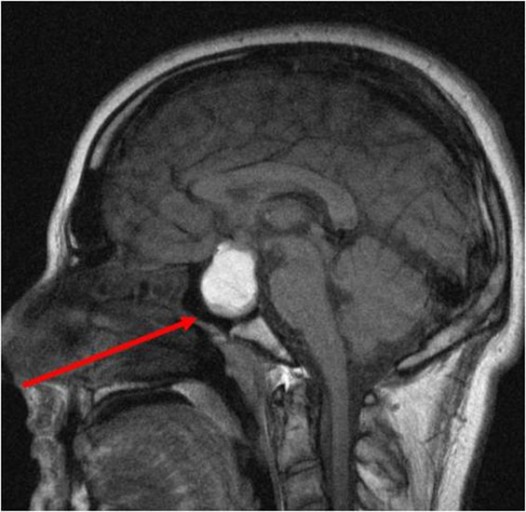

3. 진단

CT, MRI 검사를 통해 진단할 수 있고, 뇌하수체선종이 의심되는 경우, 뇌하수체에서 분비되는 호르몬의 양을 측정합니다.